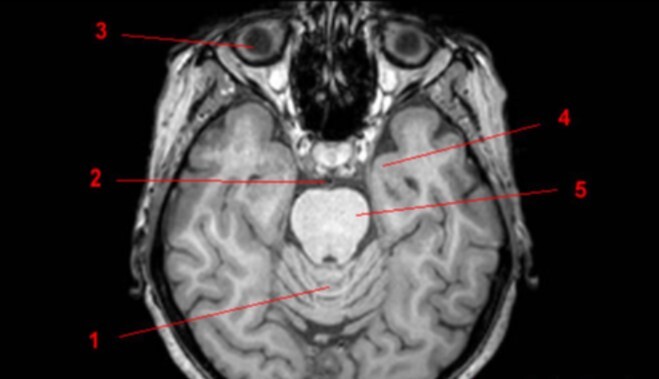

Label 1-3

1-Lt Optic nerve

2-Optic chiasm

3-Rt Optic tract

Label 1,10,12

1=Lt cerebral peduncle (midbrain)

10=Interpeduncular cistern

12=Cerebral aqueduct

Label 7-11

7=Rt Internal carotid artery

8=Optic chiasm

9=Pituitary gland

10-Lt lateral ventricle

11=Lt Cavernous sinus